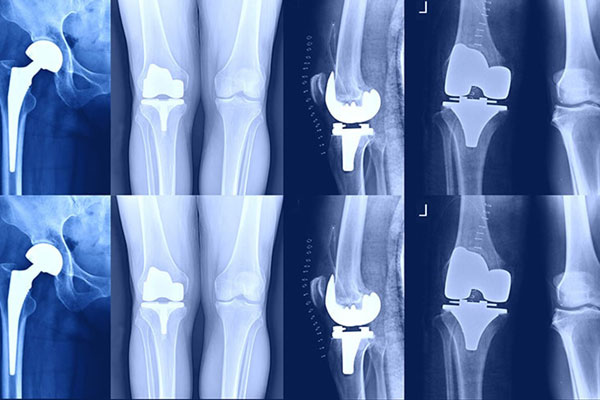

رادیوگرافی ساده (X-ray)

رادیوگرافی ساده، قدیمیترین و پرکاربردترین روش تصویربرداری است که از اشعه ایکس برای مشاهده ساختارهای داخلی بدن مانند استخوانها استفاده میشود.

- شکستگی استخوان

- بررسی مفاصل